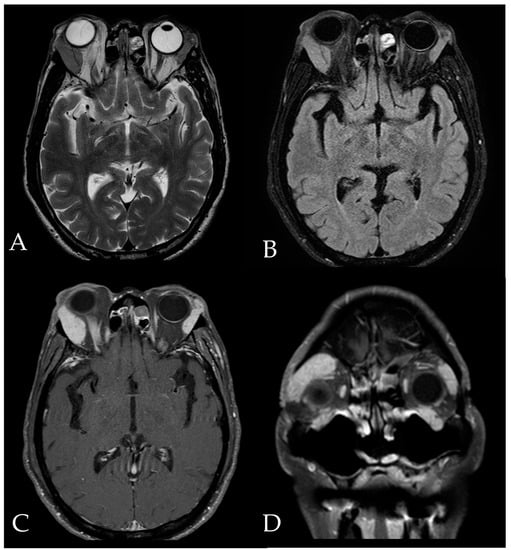

2. Case Report